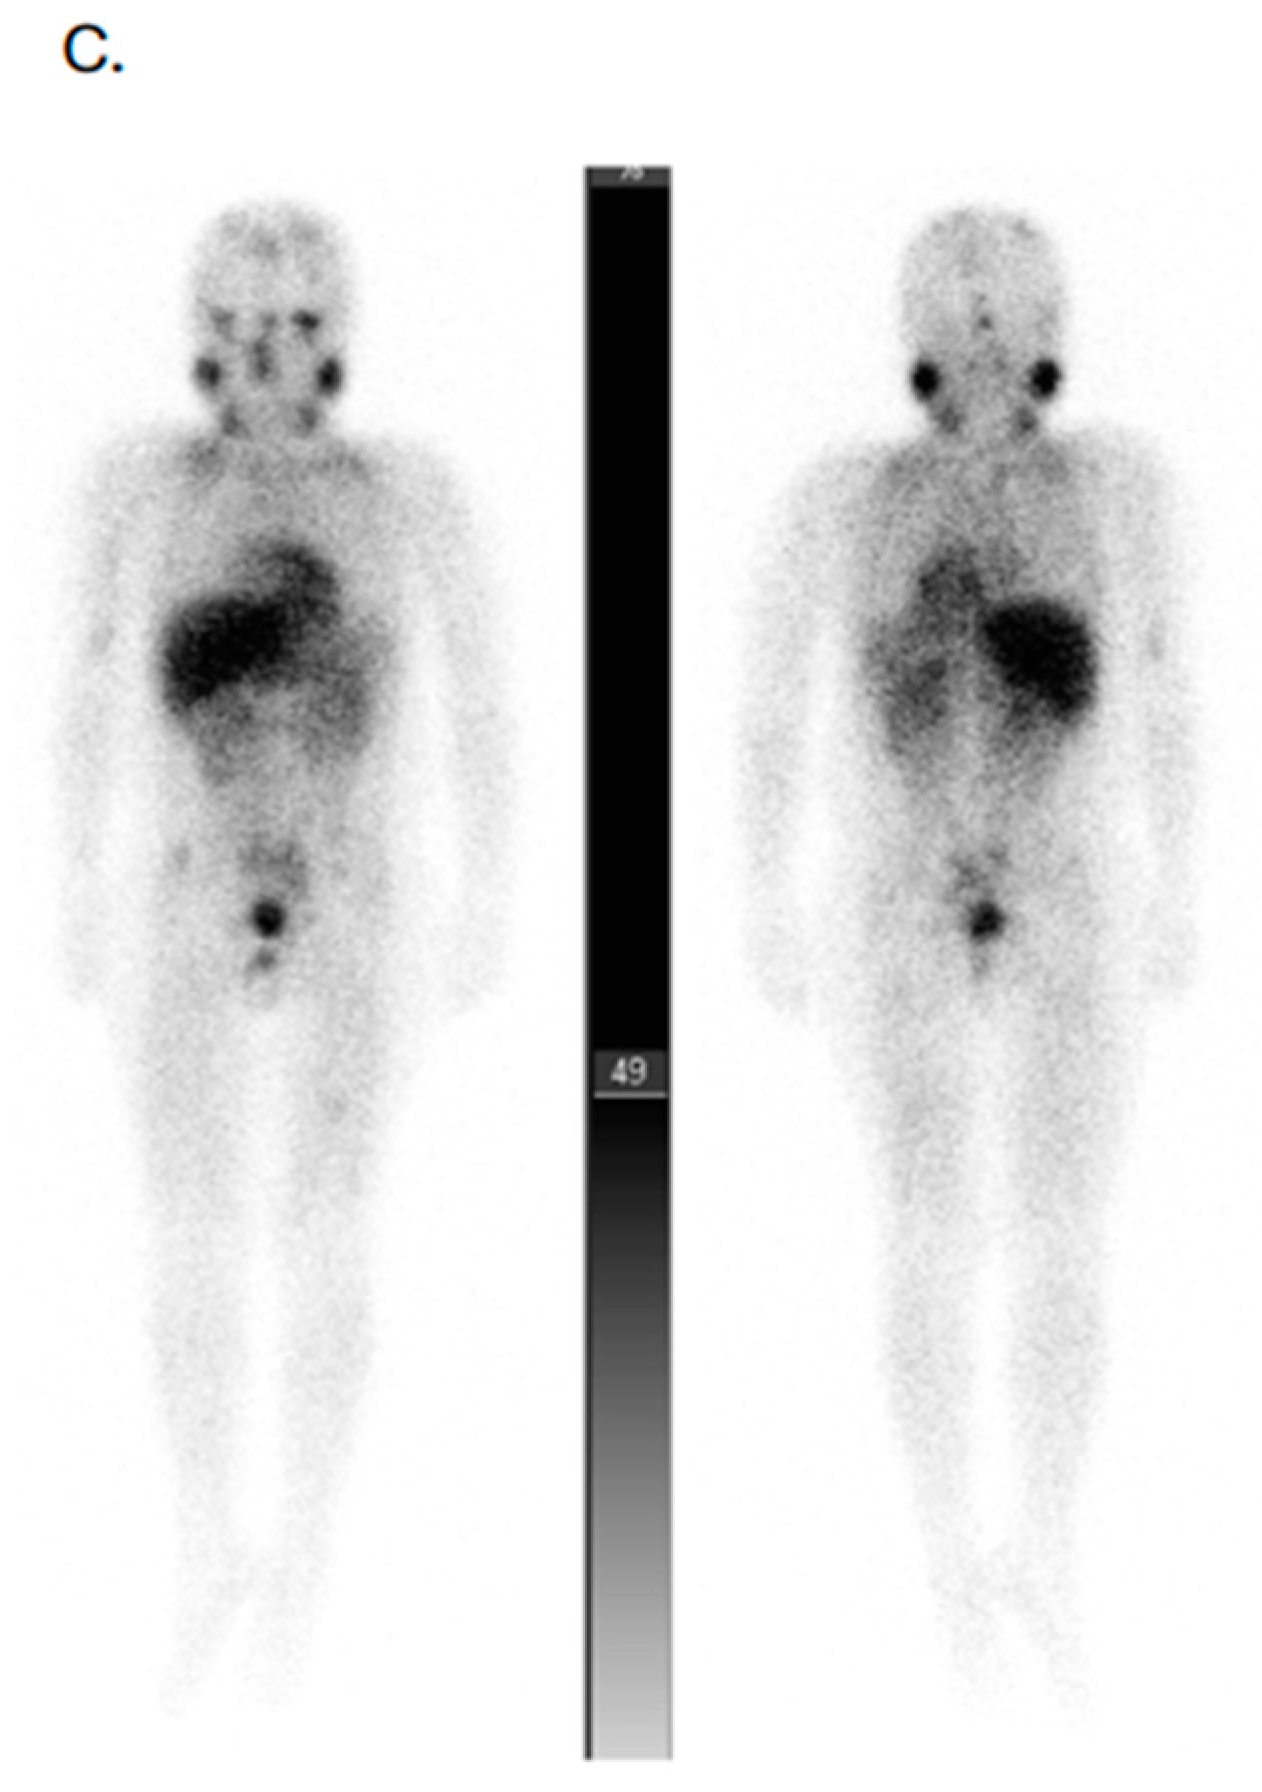

- Kong, G.; Hofman, M.S.; Murray, W.K.; Wilson, S.; Wood, P.; Downie, P.; Super, L.; Hogg, A.; Eu, P.; Hicks, R.J. Initial experience with gallium-68 DOTA-octreotate PET/CT and peptide receptor radionuclide therapy for pediatric patients with refractory metastatic neuroblastoma. J. Pediatr. Hematol. Oncol. 2016, 38, 87–96. [Google Scholar] [CrossRef]